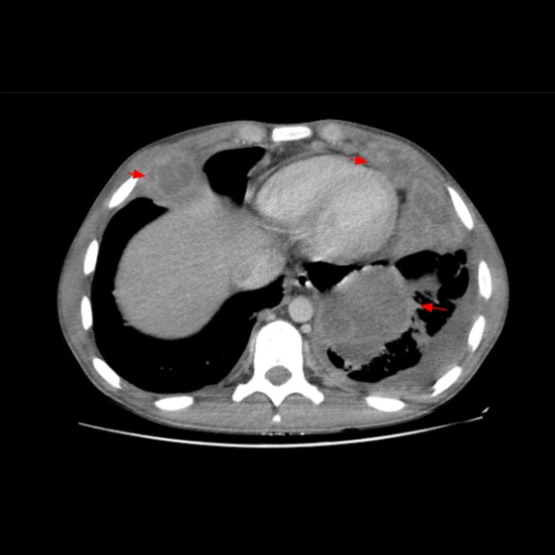

Paciente de sexo masculino de 17 años, que presenta desnutrición severa como antecedente personal, consulta por dolor abdominal en hipocondrio derecho.